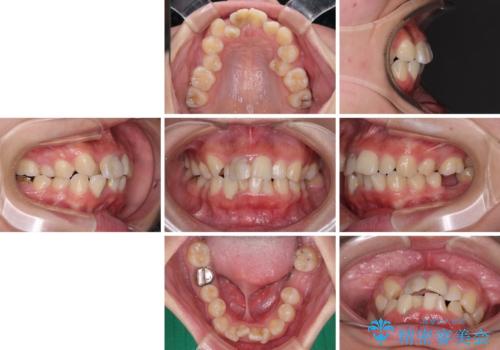

- 放置した虫歯や抜いたままの奥歯、前歯のデコボコを気にして来院された患者様です。

口元の突出感は少なく、下顎の叢生は軽微なものであったので、叢生の強い上顎左右の小臼歯を1本ずつ抜歯し、ワイヤー装置にて矯正治療を行うこととしました。

矯正治療を行う前に、根管治療の必要な上顎前歯と下顎大臼歯の根管治療を行い、矯正治療の途中で下顎の欠損部にインプラント埋入することとし、矯正治療後に補綴治療を行うこととしました。